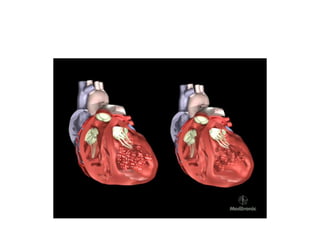

Áp lực tăng